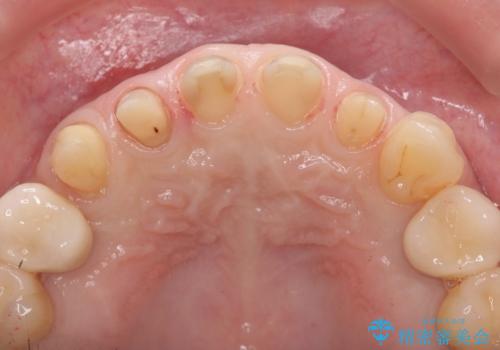

多発した前歯の重度虫歯治療

- 放置した虫歯の歯がボロボロになってしまい治療を希望され来院されました。

残根状態の歯、神経まで虫歯が達し失活した歯、歯肉縁下まで及んだ虫歯が多数認められます。

まず虫歯を拡大鏡、マイクロスコープ下で丁寧に取り除き歯肉縁下の虫歯を歯周外科により解決したのち、ジルコニアクラウン製作を行っていきます。